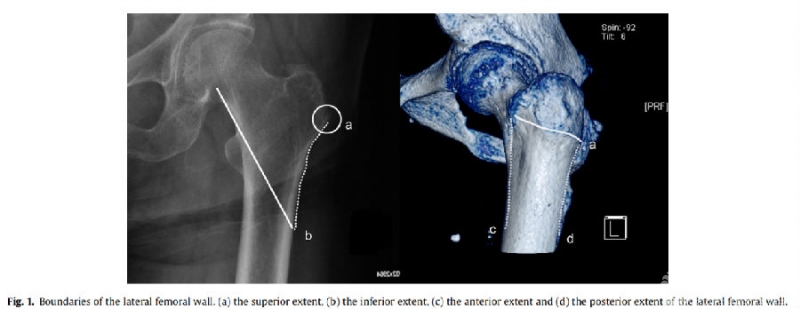

图1. 文中提出的外侧壁范围

近年来,股骨外侧壁是转子间骨折的一个研究热点,有研究表明股骨外侧壁的完整性是治疗转子间骨折的重要因素。本研究旨在探讨股骨转子间骨折合并外侧壁骨折术后内固定失败的危险因素。

结论:股骨大转子与外侧壁交界处存在游离骨块和外侧壁横行骨折线是股骨转子间骨折伴外侧壁骨折内固定失败的危险因素。股骨外侧壁的完整性与股骨转子间骨折的预后相关。股骨转子间骨折合并外侧壁骨折时,可能需要重建股骨外侧壁。